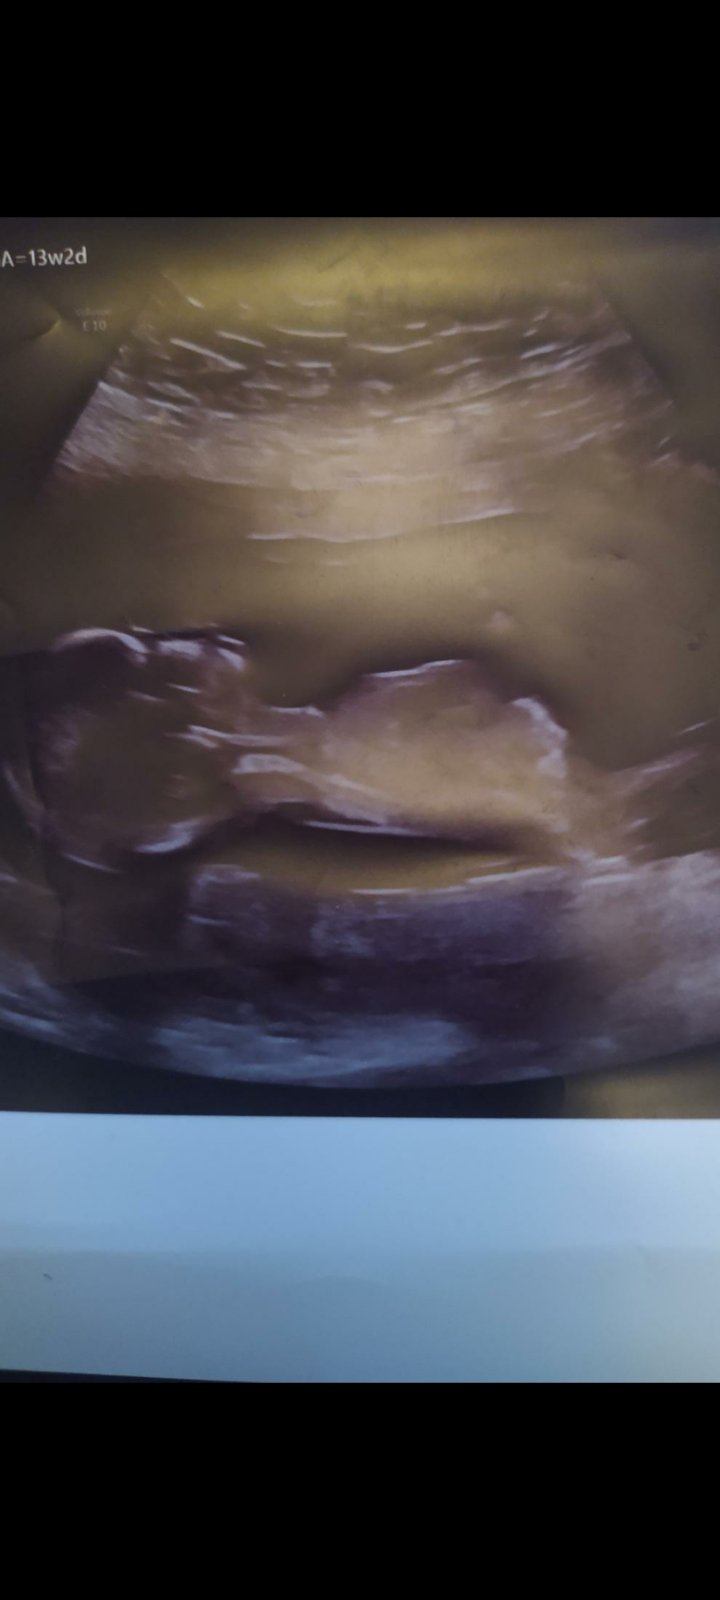

Poznáte pohlaví miminka z ultrazvukové fotky?

Na té fotce pohlavní hrbolek není, vždyť to dítě konci nekde v pase. Z toho se asi moc nepozná.

@charlotte28 Řekla bych kluk, ale fotku by to chtělo nahrát naopak. Když pootočím mobil, tak se otočí i fotka.

Z této fotky opravdu nelze poznat pohlaví.